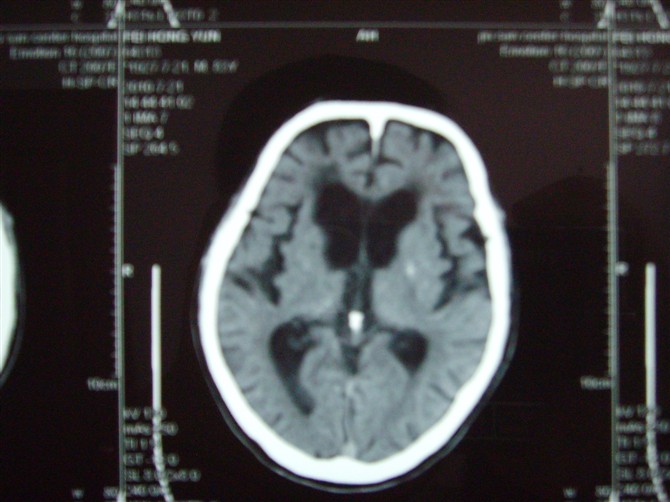

标题: CT27993:男 83岁 头晕伴双下肢无力一天 [打印本页]

标题: CT27993:男 83岁 头晕伴双下肢无力一天

脑白质疏松症,脑萎缩,复查

脑萎缩。伴小脑齿状核、苍白球钙化.脑白质脱髓鞘病变

脑白质疏松症,脑萎缩!

脑萎缩,脑白质疏松症。

1)双侧小脑半球脑软化灶。2)全脑萎缩。3)脑白质病。